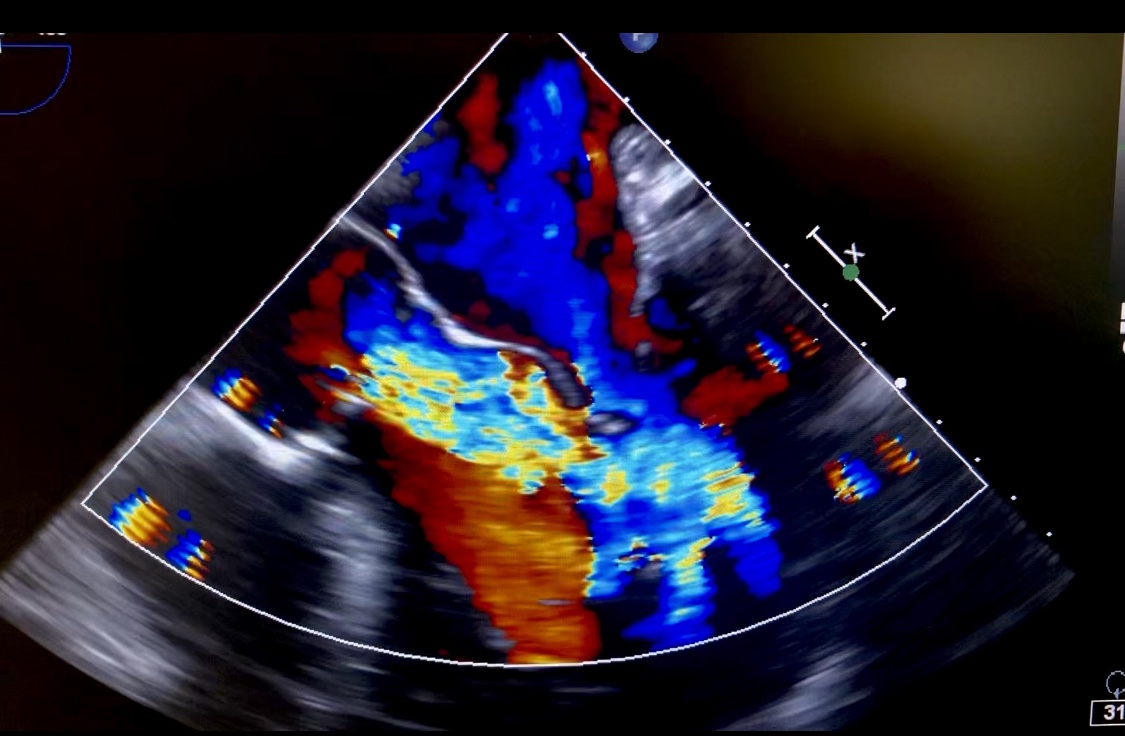

50 y/o male admitted to the hospital for progressive SOB. EF 10% on admission. Tuned up for a few weeks b4 surgery and brought to the OR for MVR. You hook up monitors. Resting HR is 130 bpm. After careful induction you obtain the following images.

Looks like severe eccentric anteriorly directed MR. Probably a P2 flail. How is this dude getting any forward flow at all with that bad of MR and a **** LV? What were the PAPs on this guy?

Yup p2 flail with several ruptured chords very obvious on 3D. After 2 weeks of tuning up this patient his EF is definitely higher. Probably closer to 35% (he came in with acute decompensated CHF)

D-shaped LV/septal flattening indicative of RV pressure/volume overload (going too fast for my eyeballs to tell if it's more during systole vs diastole). Is that like an RV aneurysm or something? It's ballooned out so far around the LV it's definitely more than your usual crescent shape.

Even before getting to the third image, one can tell from looking at the 3D full volume that the TV annulus is enormous, the RV is likely severely enlarged, and significant TR might be present. The TG SAX reveals that RV function is also mildly to moderately reduced. May also need TV banding and significant inotropic support/NO.